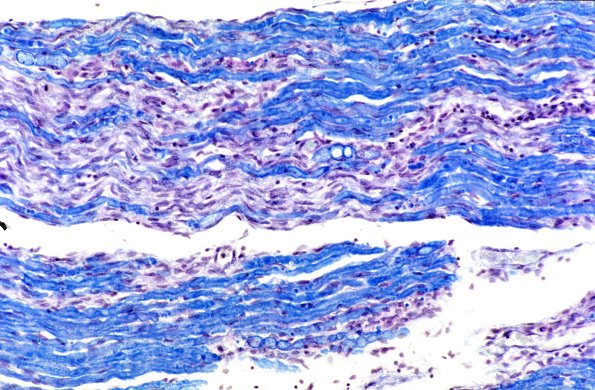

Case 9 History ---- The patient was a 17 year old male with a clinical course compatible with Guillain-Barre syndrome. He expired when his tracheotomy tube eroded anteriorly into the brachiocephalic artery and he hemorrhaged into his lungs. ---- 9A1,2 The dorsal and ventral spinal roots in longitudinal section showed patchy loss of myelin (LFB-PAS, 9A1) with relative preservation of axons (Bodian, 9A2)